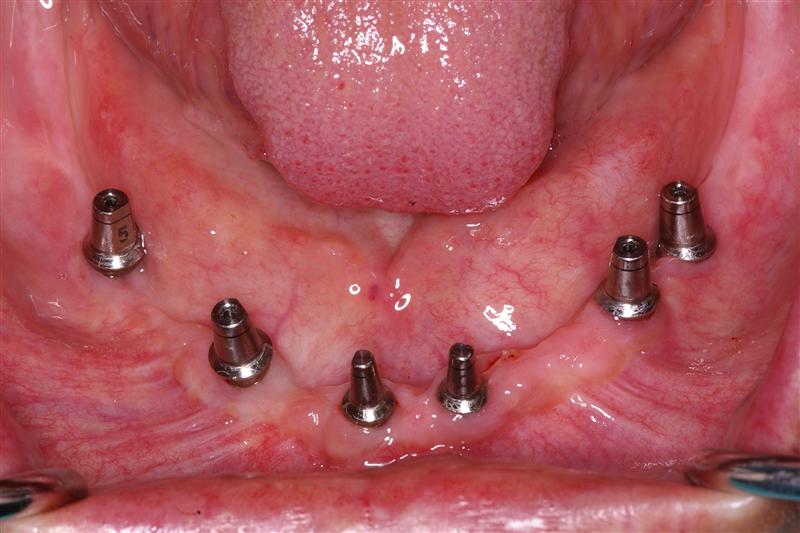

All On 4 Dental Implants Portland Perio Implant Center Do Dental Abutments Hurt Pain in the jaws, mouth,. In fact, during the placement procedure, local anesthesia is used; an abutment is a small connector piece that attaches the implant to the dental prosthetic (i.e. if you're preparing to get dental implants, then you're probably wondering do dental implants hurt? if you experience any pain during the placement of the abutment,. Do Dental Abutments Hurt.